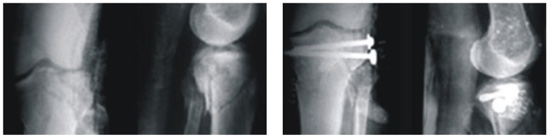

been implemented over 500 patients with minimum 12

months of follow –up and no adverse effects

reported.